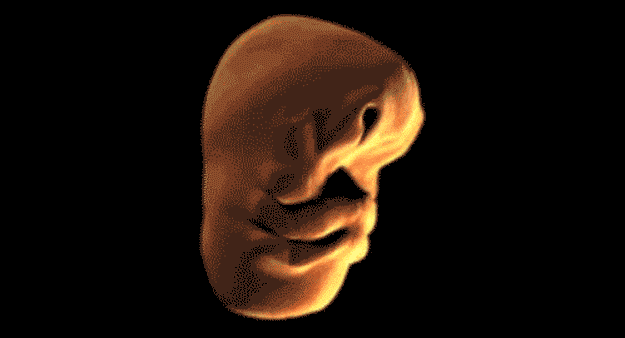

Как формируется лицо ребенка в утробе